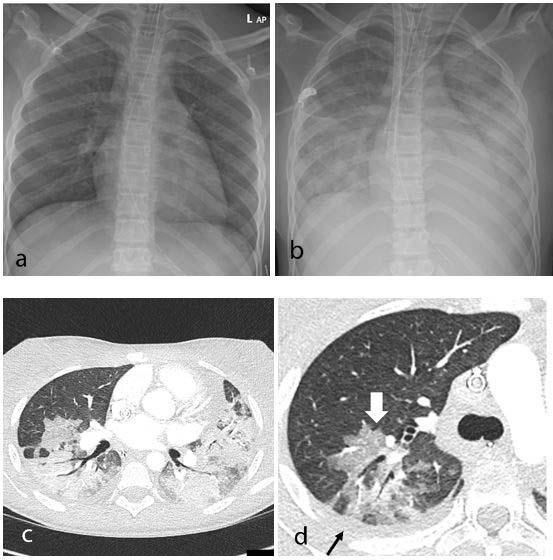

image: Thoracic findings in a 15-year-old girl with Multisystem Inflammatory Syndrome in Children (MIS-C). (a) Chest radiograph on admission shows mild perihilar bronchial wall cuffing. (b) Chest radiograph on the third day of admission demonstrates extensive airspace opacification with a mid and lower zone predominance. (c, d) Contrast-enhanced axial CT chest of the thorax at day 3 shows areas of ground-glass opacification (GGO) and dense airspace consolidation with air bronchograms. (c) This conformed to a mosaic pattern with a bronchocentric distribution to the GGO (white arrow, d) involving both central and peripheral lung parenchyma with pleural effusions (black small arrow, d).

The array of findings includes airway inflammation and rapid development of pulmonary edema, coronary artery aneurysms, and extensive intra-abdominal inflammatory changes.

The study identified a pattern of imaging findings in post COVID-19 MIS-C, including airway inflammation, rapidly progressive pulmonary edema, coronary artery aneurysms and extensive abdominal inflammatory changes within the right iliac fossa.

All 35 children underwent chest X-ray due to fever, sepsis or features of multisystem inflammation. Nineteen X-rays were abnormal, the most common finding being that of bronchial wall thickening.

The predominant findings on chest CT were basal consolidation, or part of the lung filling with fluid; and collapsed lung with pleural effusions, or build-up of fluid in the outer membranes of the lungs.